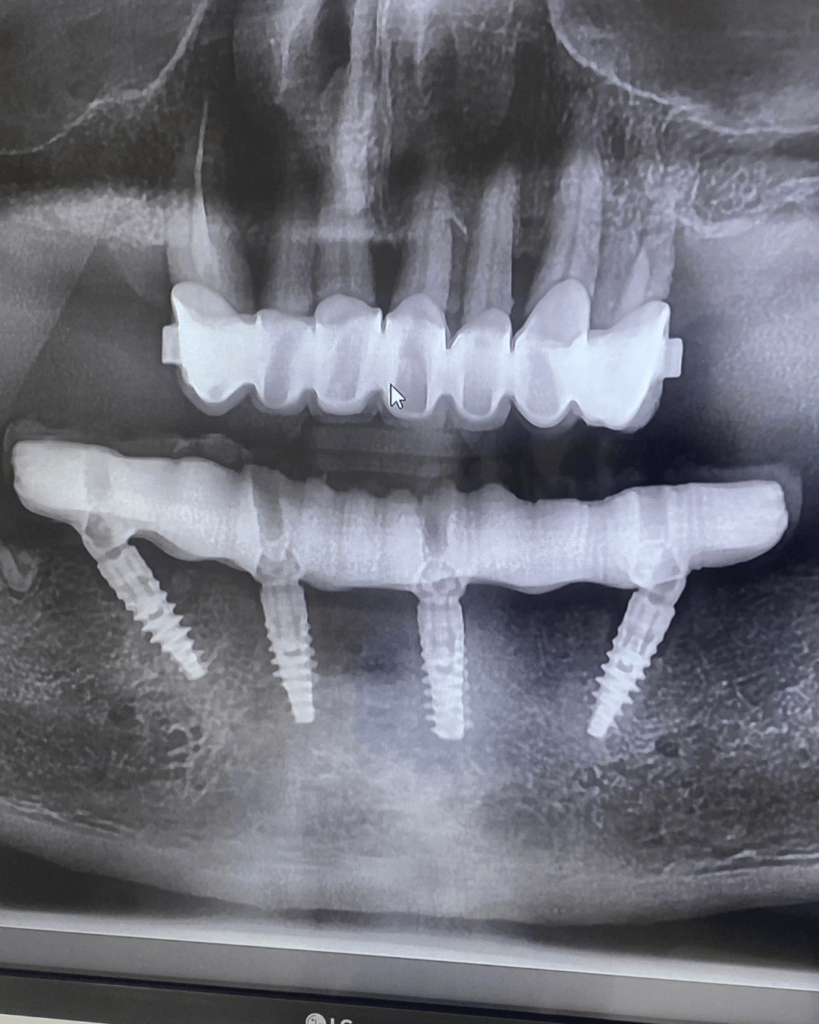

Nel nostro Studio Dentistico in centro a Faenza, una affiatata equipe di professionisti esperti nelle più avanzate tecniche di implantologia esegue impianti dentali di ultima generazione, come gli impianti dentali a carico immediato o gli impianti dentali All On 4.

Gli impianti dentali All On 4 permettono di riabilitare con denti fissi un’intera arcata dentale posizionando solo 4 impianti osteointegrati. Gli impianti dentali All On 4 utilizzano perni realizzati in titanio (utilizziamo impianti che vengono sottoposti a severe certificazioni statunitensi ed europee come la FDA) che vengono inseriti nell’osso. L’impianto endosseo diventa così parte dell’organismo, riabilitando l’arcata dentale compromessa.